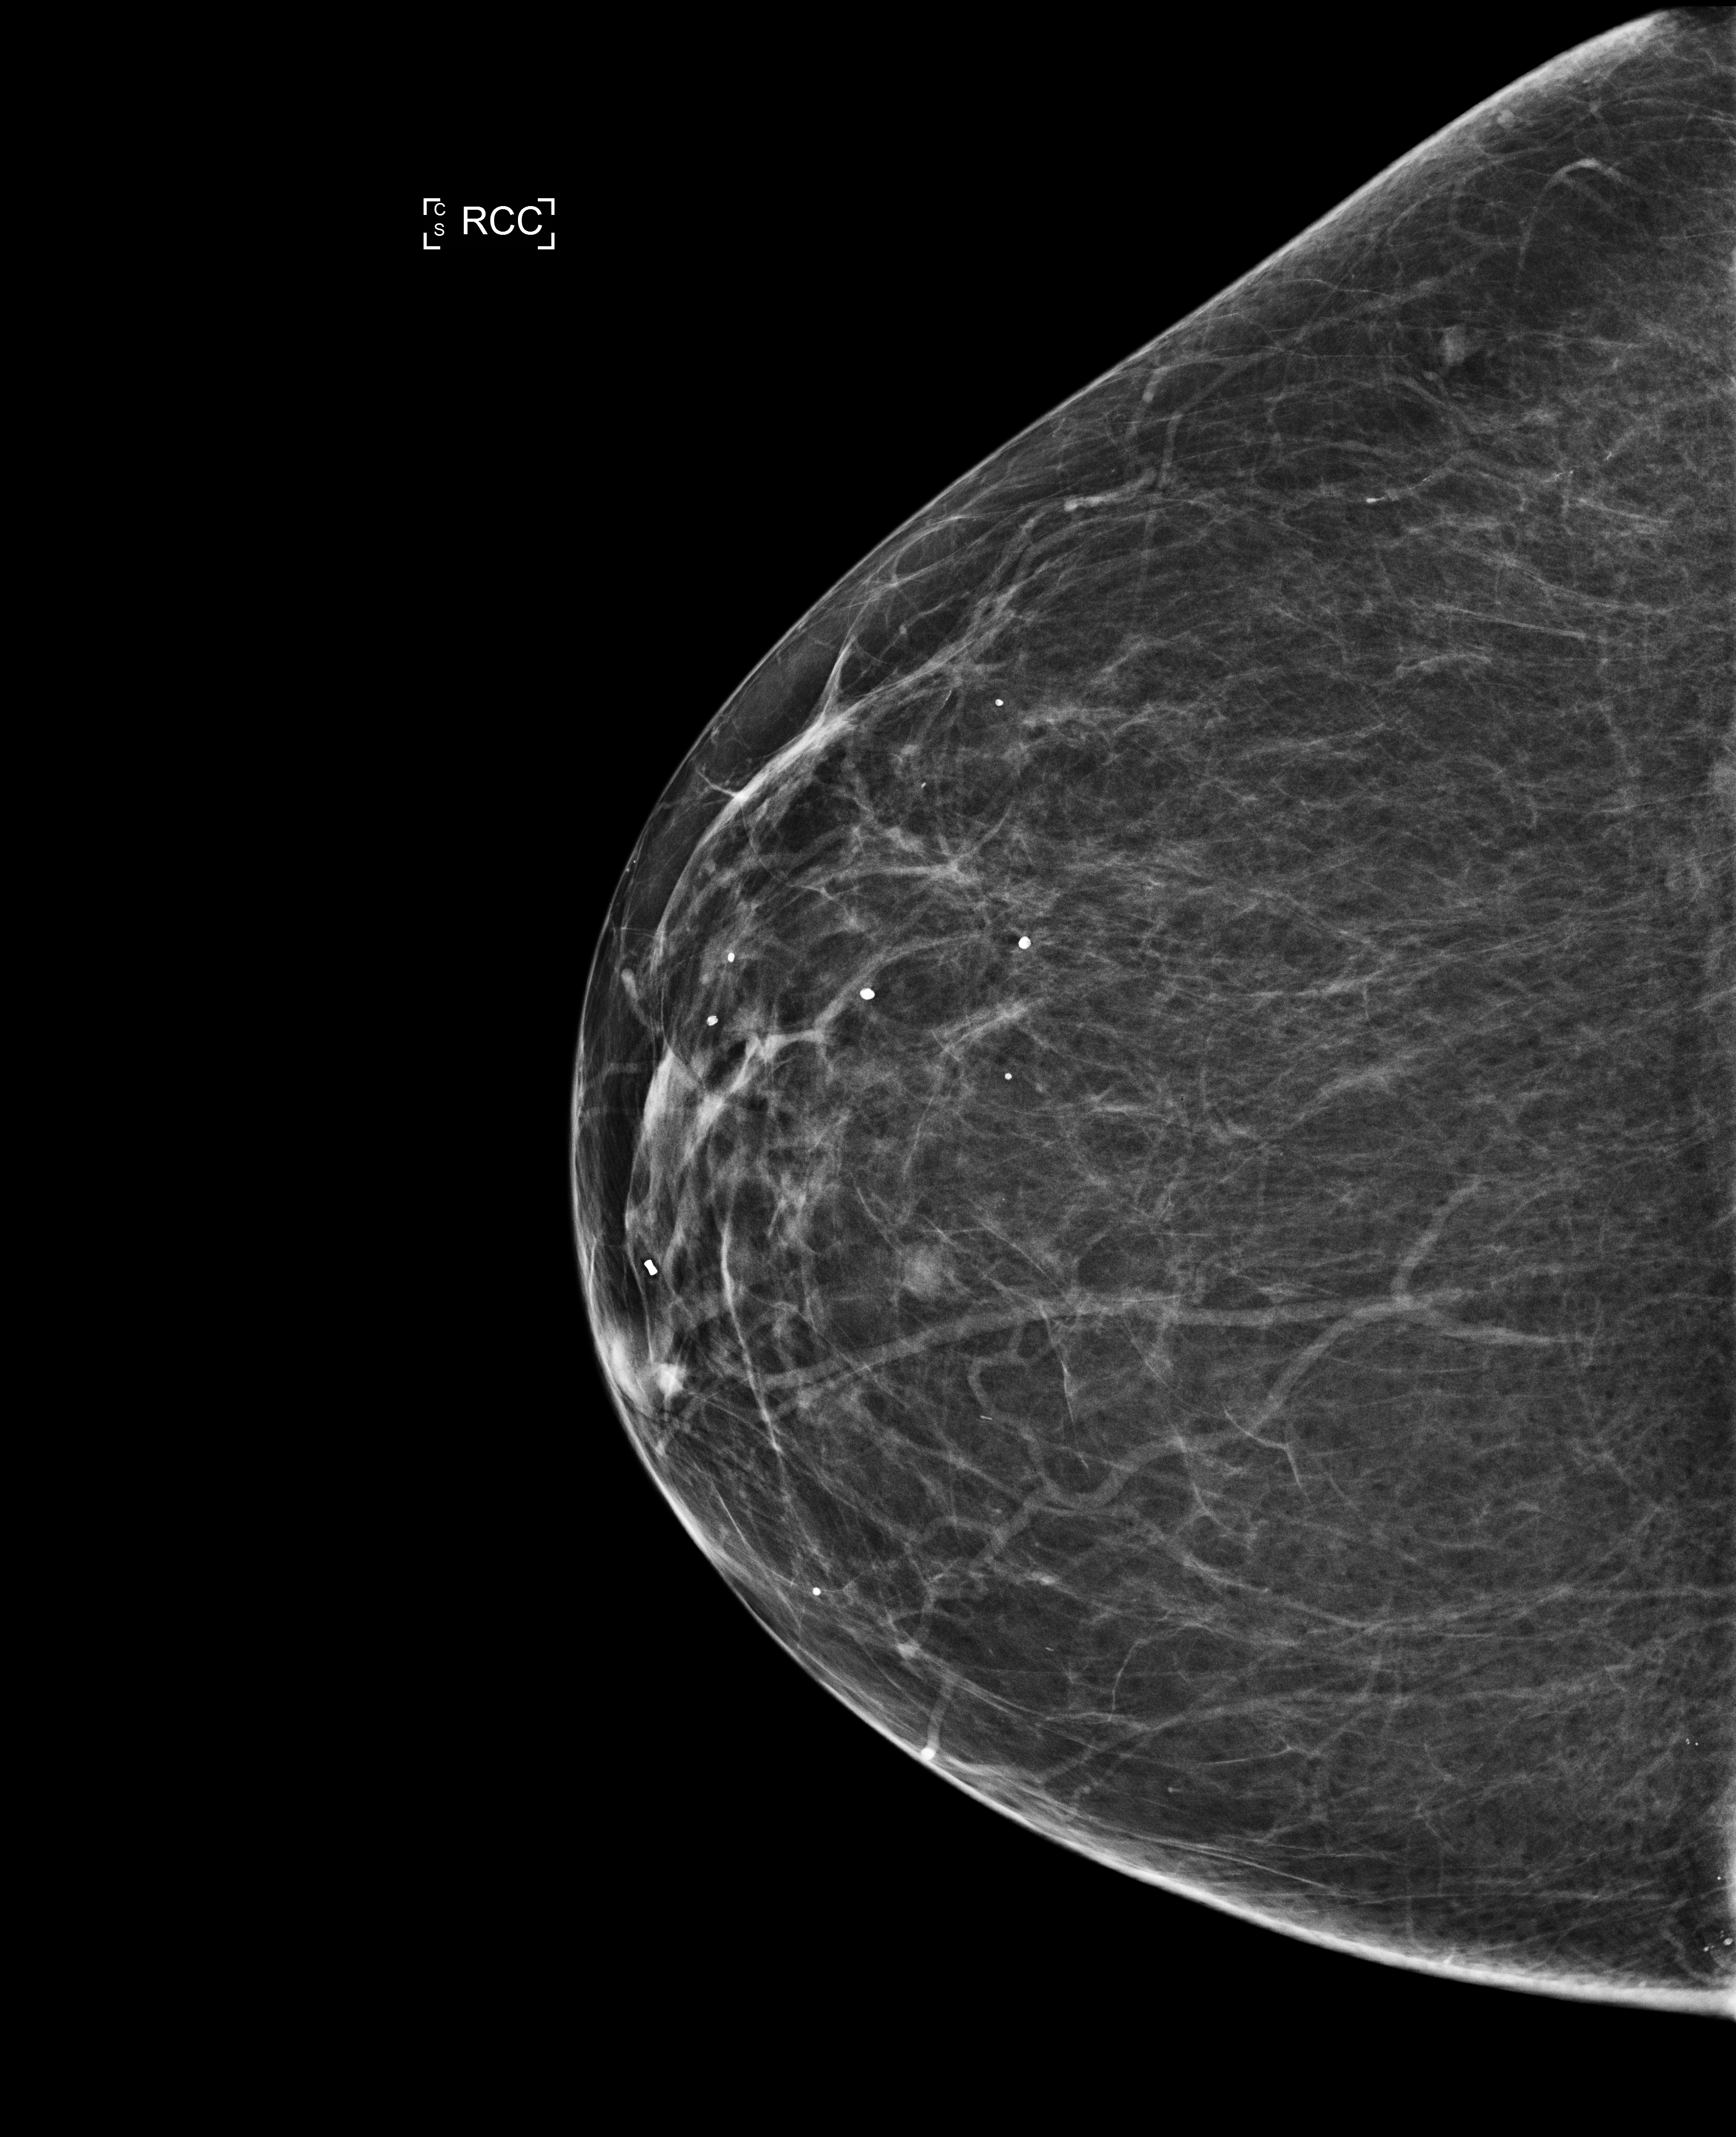

Phân loại Bi-RADS

Phân loại BI-RADS (Breast Imaging Reporting and Data System- BI-RADS)